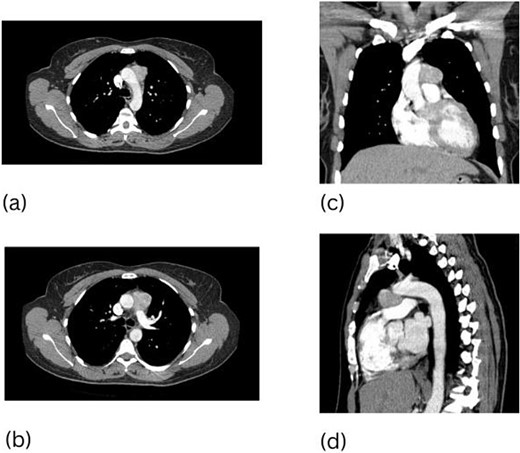

A 66-year-old woman presented with generalized fatigue and chronic cough. A CT scan of her chest revealed a 3.5 cm paraganglioma in the AP window as well as a 1.6 cm left adrenal mass (Fig. 3). Mediastinal paraganglioma resection was performed via median sternotomy with 67 min of CPB. The mass in this patient was densely attached to the ascending aorta. Sharp dissection was carried out circumferentially around the ascending aorta and then superiorly to the arch. The inferior aspect of paraganglioma was carefully mobilized from the main pulmonary and right pulmonary arteries until mass was completely excised. Paraganglioma measured 3.5 × 3.0 × 2.0 cm with diffuse immunoreactivity for chromogranin, synaptophysin, CD56, S-100, and vimentin. Patient recovered well from her surgeries with postoperative annual imaging revealing no recurrence for 5 years.

CT scan of the chest, 3.5 cm paraganglioma with necrotic center (a–c).